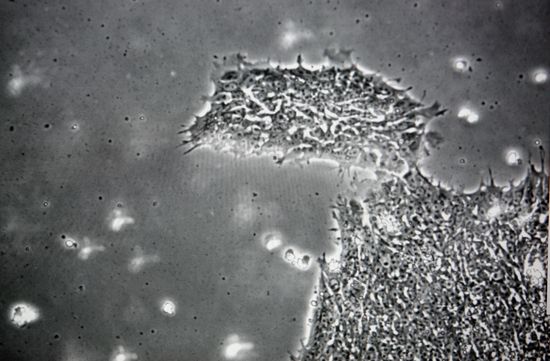

(Photo: A colony of human embryonic stem Cells is seen on a computer monitor the is hooked up to a microscope at the Wisconsin National Primate Research Center at University Wisconsin-Madison March 10, 2009 in Madison, Wisconsin. On March 9, 2009 President Barack Obama signed an order reversing the Bush administration's limits on human embryonic stem cell research. By Darren Hauck/Getty Images.)